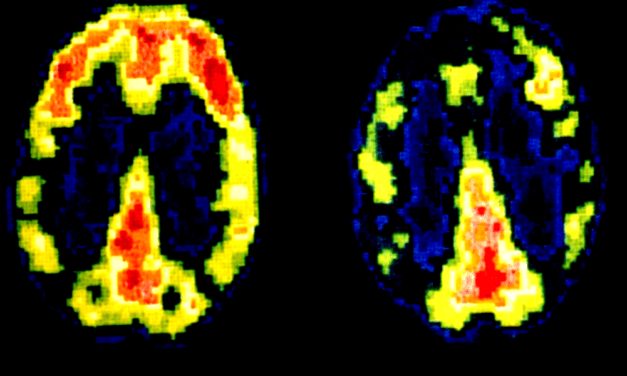

Wie das Gehirn eines Mörders aussieht

Ist es falsch, Inhaftierte im Gefängnis zu bestrafen? Diese Frage stellte der Neurokriminologe Adrian Raine kürzlich im Wiener Volkstheater bei der wieder aufgenommenen Veranstaltungsreihe TEDx Vienna. Den Drang nach Vergeltung dürften vor allem Menschen, die Opfer einer Straftat geworden sind, nachempfinden können. Wie Raine selbst, der im Urlaub eines Nachts einen Einbrecher davon abhielt, ihn…